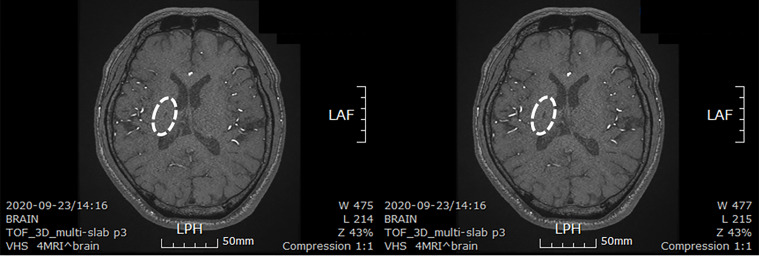

患者在干細(xì)胞移植后約30個(gè)月拍攝腦部CT圖像以確認(rèn)病灶的大小。病灶縮小至0.6cm×0.3cm(圖4)。

圖4:微創(chuàng)人臍帶間充質(zhì)干細(xì)胞移植后患者的腦部計(jì)算機(jī)斷層掃描圖像。

圖4